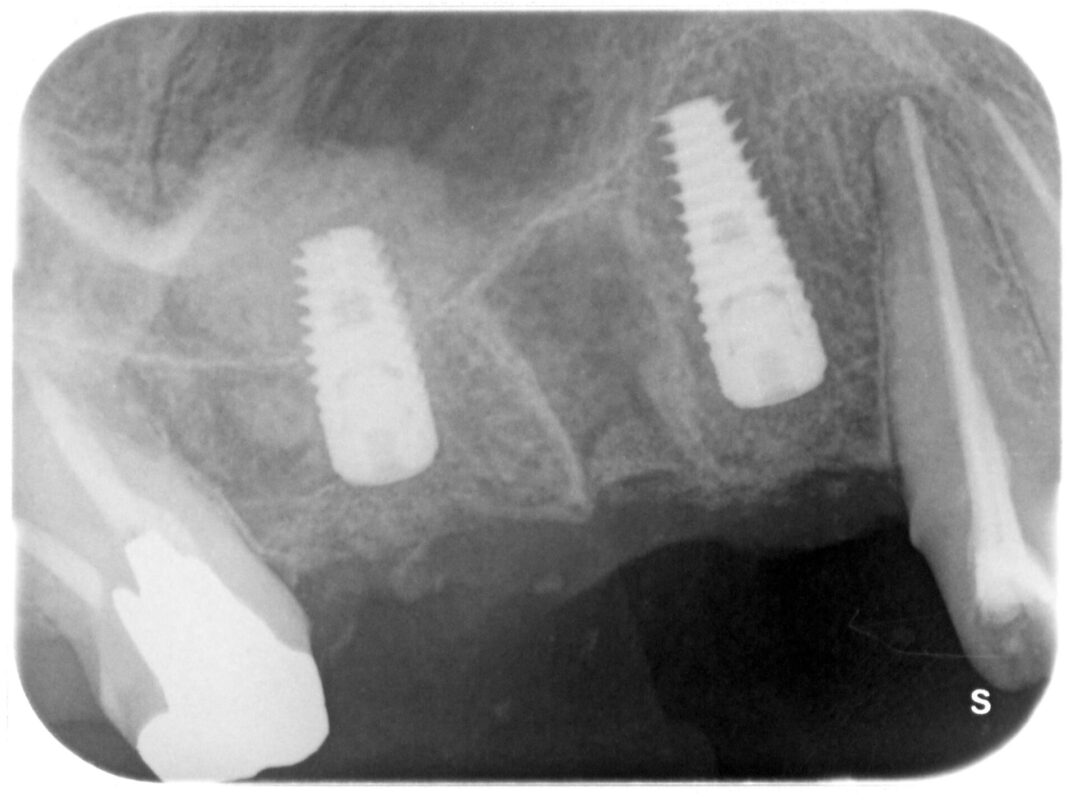

術中

左側インプラントの上の「雲」のようなものが移植した骨です。

右側のインプラントは上顎洞底ギリギリのところでストップさせています。

処置時間は40分程度です。

使用インプラントはプライムテーパー(スウェーデン)。